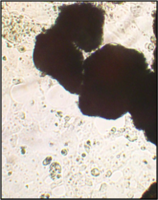

Образец исследуемого материала (аллогенный ГАП серии «Лиопласт»® массой 2 мг) помещали на равномерный монослой фибробластов плотностью 332 клетки/ммІ.

Этот материал имеет щелочную реакцию (рН от 8 и выше).

Через сутки вокруг образца образуется зона гибели клеток шириной 2,1±0,14 мм.

Граница этой зоны довольно резкая.

За зоной отсутствия клеток монослой до края чашки практически не отличается от монослоя в контрольных чашках.

В 5-6 сериях экспериментов при изучении кристаллического материала минерального компонента костной ткани «аллогенного гидроксиапатита», получаемого по технологии «Лиопласт», отмечалась гибель клеток в непосредственной близости от материала.

Альтерация прилежащих к биоимплантату клеток приводила к выходу медиаторов в культуральную среду.

При этом повышалась пролиферативная активность неповрежденных прилежащих клеток и клеток отдаленной зоны.

С 3-х суток, когда рН среды во флаконе выравнивалась, начиналось быстрое зарастание дна флакона. К 4 суткам монослой полностью восстанавливался.